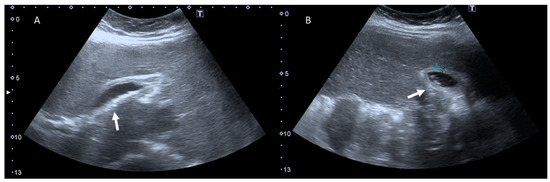

4. Clinical Setting: Abdominal Pain

6. Biliary Tract and Pancreatic Diseases

7. Ureterolithiasis